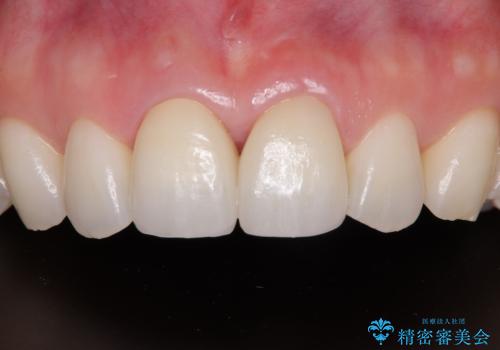

保険診療の黄ばんできた前歯をオールセラミッククラウンで自然な歯に